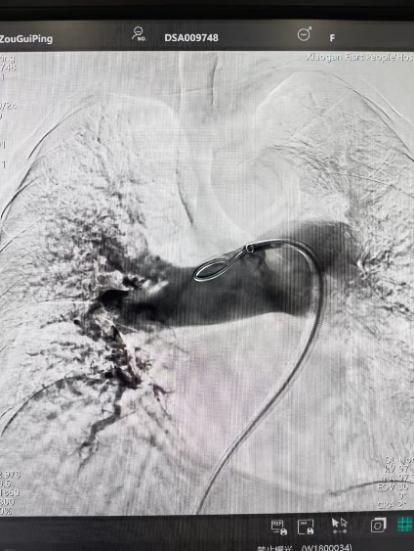

術(shù)前

術(shù)后

手術(shù)在局部麻醉下進(jìn)行,團(tuán)隊(duì)通過(guò)股靜脈穿刺,將專用抽栓導(dǎo)管精準(zhǔn)送達(dá)肺動(dòng)脈栓塞部位,利用負(fù)壓抽吸技術(shù)成功清除大量血栓;隨后,在血栓局部精準(zhǔn)灌注溶栓藥物,進(jìn)一步溶解殘余血栓,恢復(fù)肺部血流灌注;同時(shí),為防止下肢深靜脈血栓再次脫落引發(fā)肺栓塞,團(tuán)隊(duì)為患者置入下腔靜脈濾器,整個(gè)手術(shù)歷時(shí)約1小時(shí)。術(shù)后,鄒婆婆呼吸困難癥狀即刻得到緩解,血氧飽和度顯著提升,右心負(fù)荷明顯減輕,目前身體狀況正在逐步恢復(fù)中。